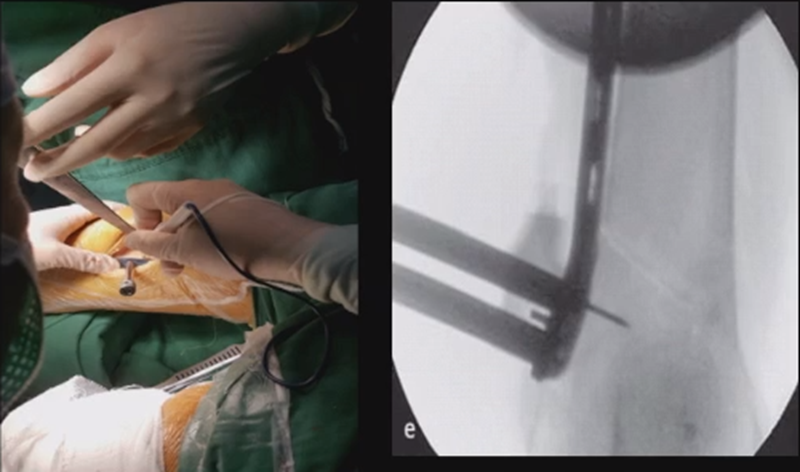

5、闭合固定

处理完后,紧密闭合截骨端。

然后核实力线,如力线位置良好,就可以采用内固定的方式将位置维持好。

对于术中出现的合页骨折,此时还有一定的稳定性,可以调整力线固定以后,由前外向后内打一根防旋螺钉,这样仍然是比较稳定,术后康复计划与正常一样。

对于术中合页骨折,但非常不稳定、无法控制力线的情况,可以由外侧向股骨外髁打入一枚2.0的克氏针,因为克氏针具有一定弹性,相当于重建合页临时稳定性,在此基础上再去调整力线,做固定。

近端螺钉松开,调整力线,重新固定后,在外侧加小钢板抗旋。